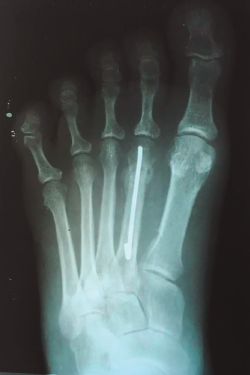

- La retirada del alambre se realizó solo en caso de infección del trayecto del mismo o cuando se constató consolidación ósea radiológicamente (usualmente en la octava semana), como en la Figura 2.

Figura 2. Consolidación radiológica del foco de fractura del cuello del segundo metatarsiano a la sexta semana postoperatoria.

De las 12 fracturas de metatarsianos, 11 de ellas (91,66%) presentaron signos de consolidación ósea para el control de la octava semana, como se representa en la Figura 2. Solo en un paciente una de las fracturas de metatarsianos (8,34%) presentó retardo en su consolidación, que alcanzó a la décima semana.